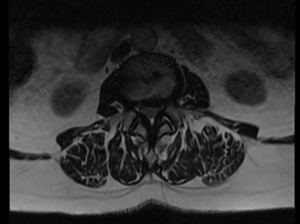

Sténose du canal lombaire L2-L3 avant et après chirurgie de décompression.